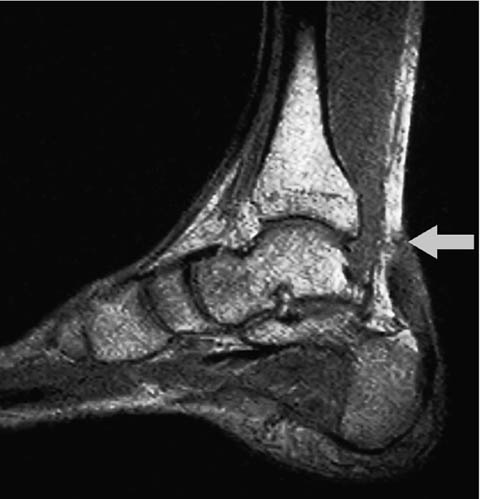

39歳の男性.野球の試合中にジャンプしてボールをキャッチした着地時に,踵に疼痛と違和感とを訴えた.その直後から歩行困難となったために,応急処置の後に緊急搬送された.搬送先の病院で撮影された足部MRIを下に示す.矢印は損傷部位を示す.受傷直後の処置として